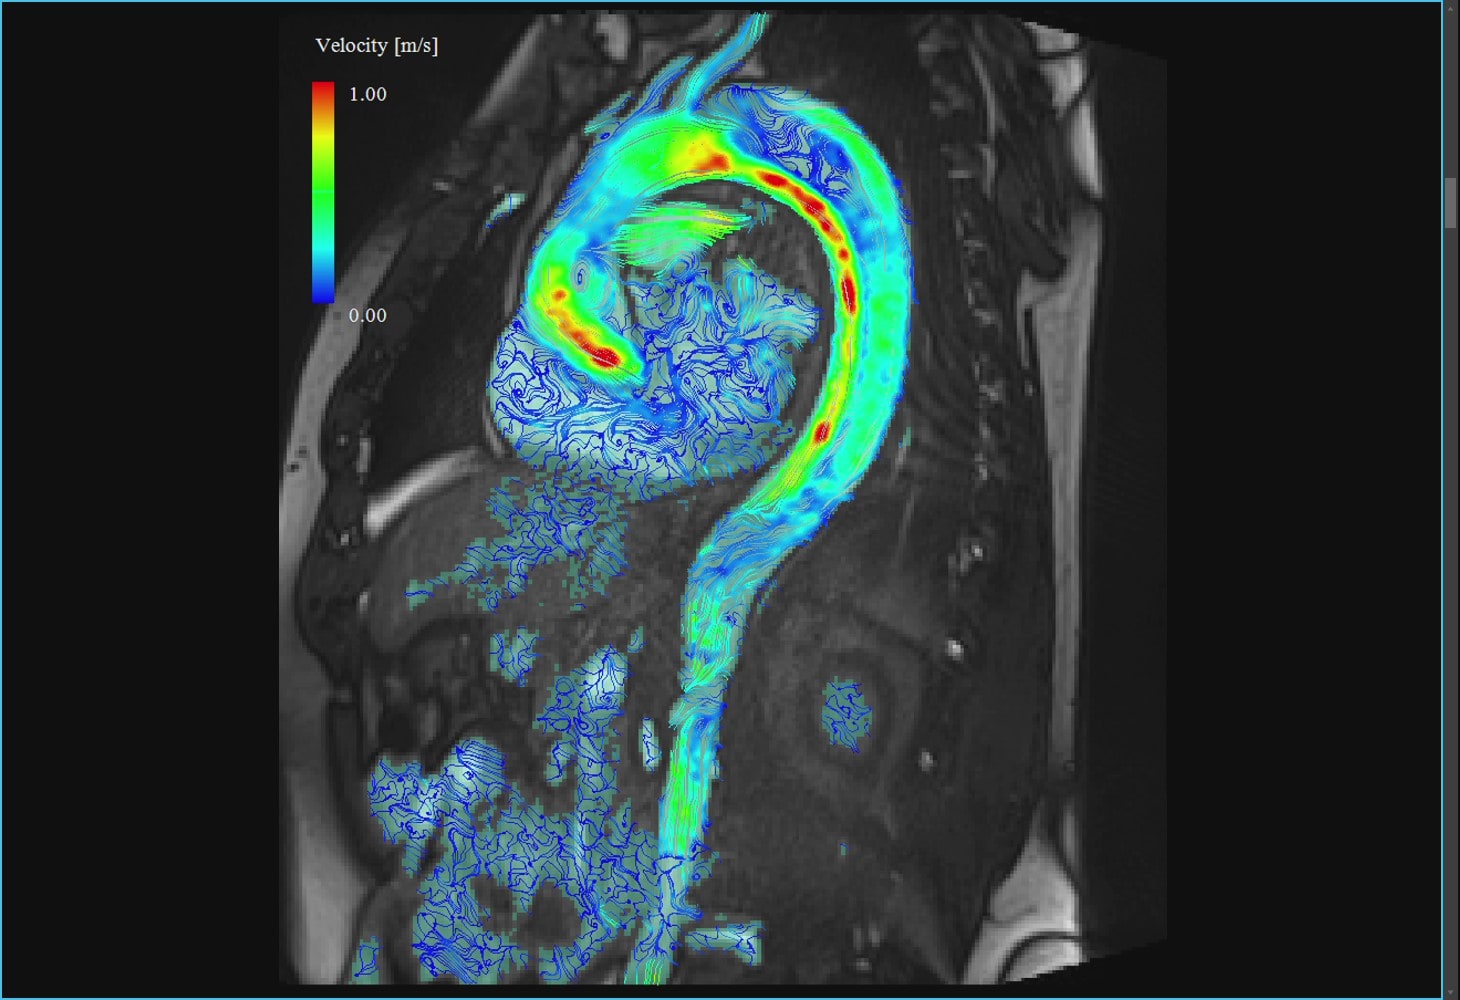

大動脈疾患の診断はCTを用いるのが一般的ですが、MRIは造影剤を用いないでも冠動脈を描出することや大動脈の血流動態の評価ができるので、造影剤アレルギーのある患者さんの血管診断に有効です。

慢性大動脈解離のMRI